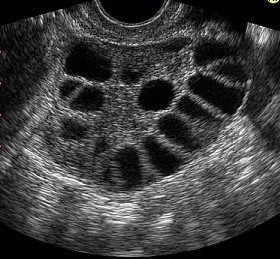

This includes menstrual history, ovulation assessment, hormone testing, ultrasound scans, and screening for conditions like PCOS, endometriosis, and fibroids.